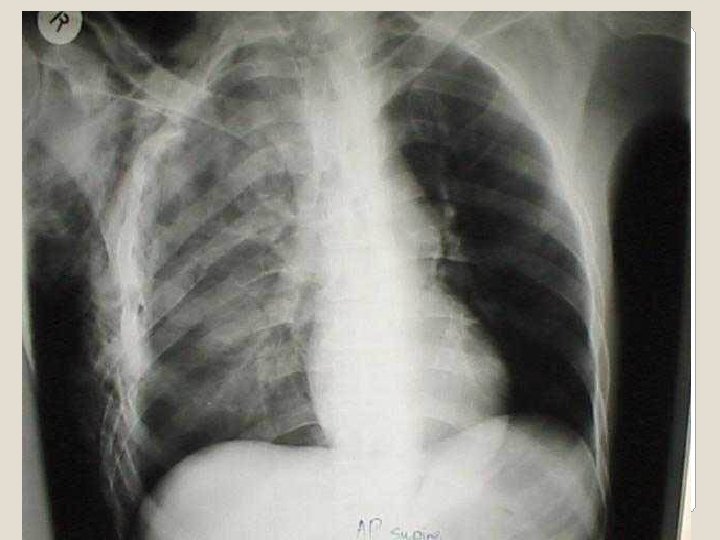

�Dengan foto toraks akan lebih jelas karena akan terlihat fraktur iga yang multipel, akan tetapi terpisahnya sendi costochondral tidak akan terlihat. �Pemeriksaan analisis gas darah yaitu adanya hipoksia akibat kegagalan pernafasan, juga membantu dalam diagnosis Flail Chest.